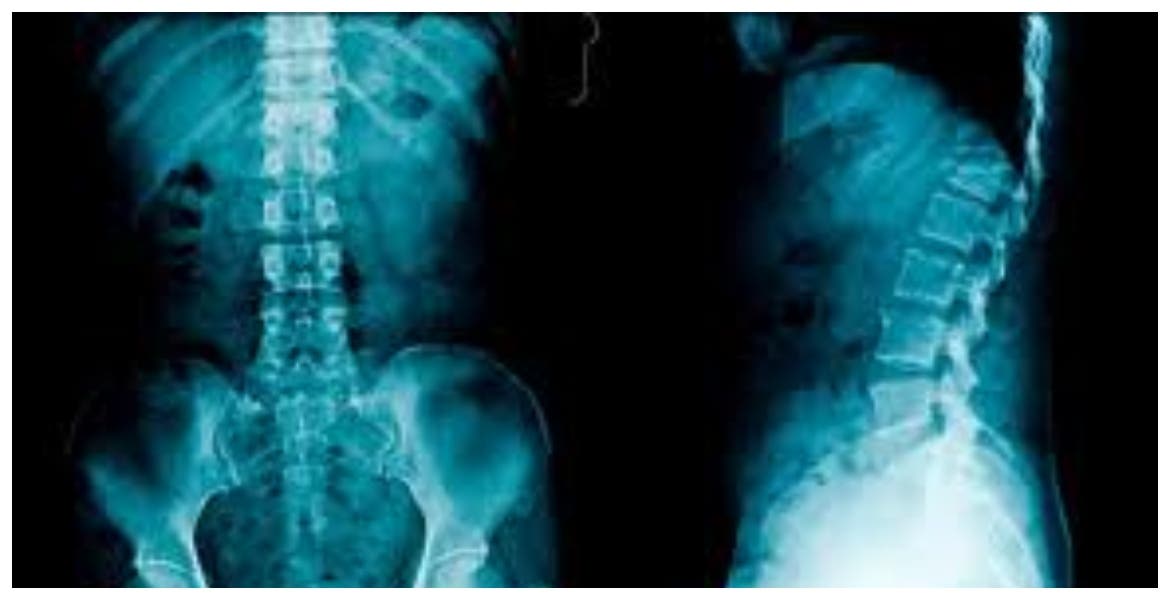

Las radiografías de la columna vertebral son imágenes de la columna vertebral. Pueden tomarse para detectar lesiones o enfermedades que afectan los discos o las articulaciones de la misma. Estos problemas pueden incluir fracturas, infecciones, dislocaciones, tumores, espolones óseos o enfermedad de disco en la columna vertebral.

También se realizan para revisar la curva de la columna vertebral (escoliosis) o para detectar defectos.

La columna vertebral está dividida en cuatro partes, de modo que hay cuatro tipos comunes de radiografías de la columna:

- Radiografía de la columna cervical. Esta prueba de radiografía toma imágenes de los 7 huesos del cuello (cervicales).

- Radiografía de la columna torácica. Toma imágenes de los 12 huesos del pecho (torácicos).

- Radiografía de la columna lumbosacra. Toma imágenes de los 5 huesos de la parte baja de la espalda (vértebras lumbares) y muestra los 5 huesos fusionados en la parte inferior de la columna vertebral (sacro).

- Radiografía del sacro/cóccix. Permite una visión detallada de los 5 huesos fusionados en la parte inferior de la columna vertebral (sacro) y los 4 pequeños huesos del cóccix.

Las radiografías de columna más comunes son de las vértebras cervicales (imágenes de la columna cervical [C]) y de las vértebras lumbosacras (imágenes de la columna lumbosacra [LS]).